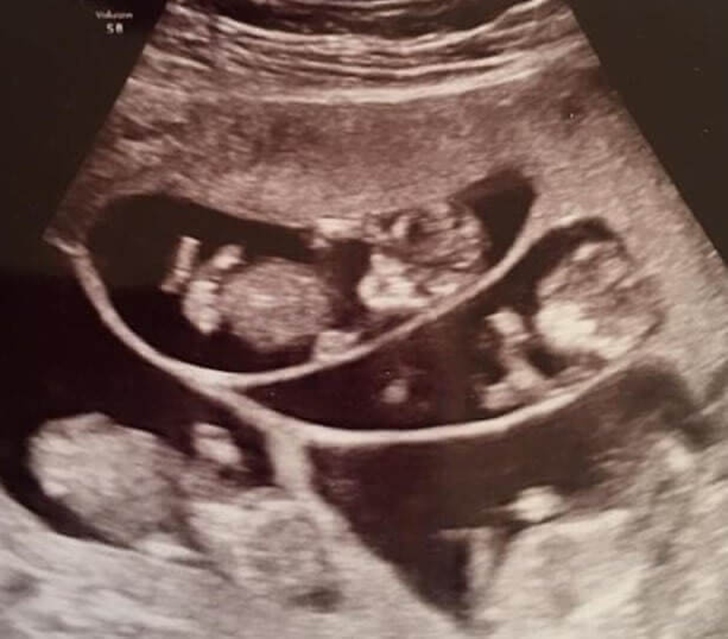

As weeks and months were leading up to the birth of seven babies, it was scary, thrilling, and stressful times for the family. The doctors were concerned that the stress of the deliveries could lead her to early labor.

Bobbi tried her best to keep calm, and though the couple was worried that things might not work as planned, they knew that staying positive was their best bet at that time. They tried their best to remain as positive as possible.